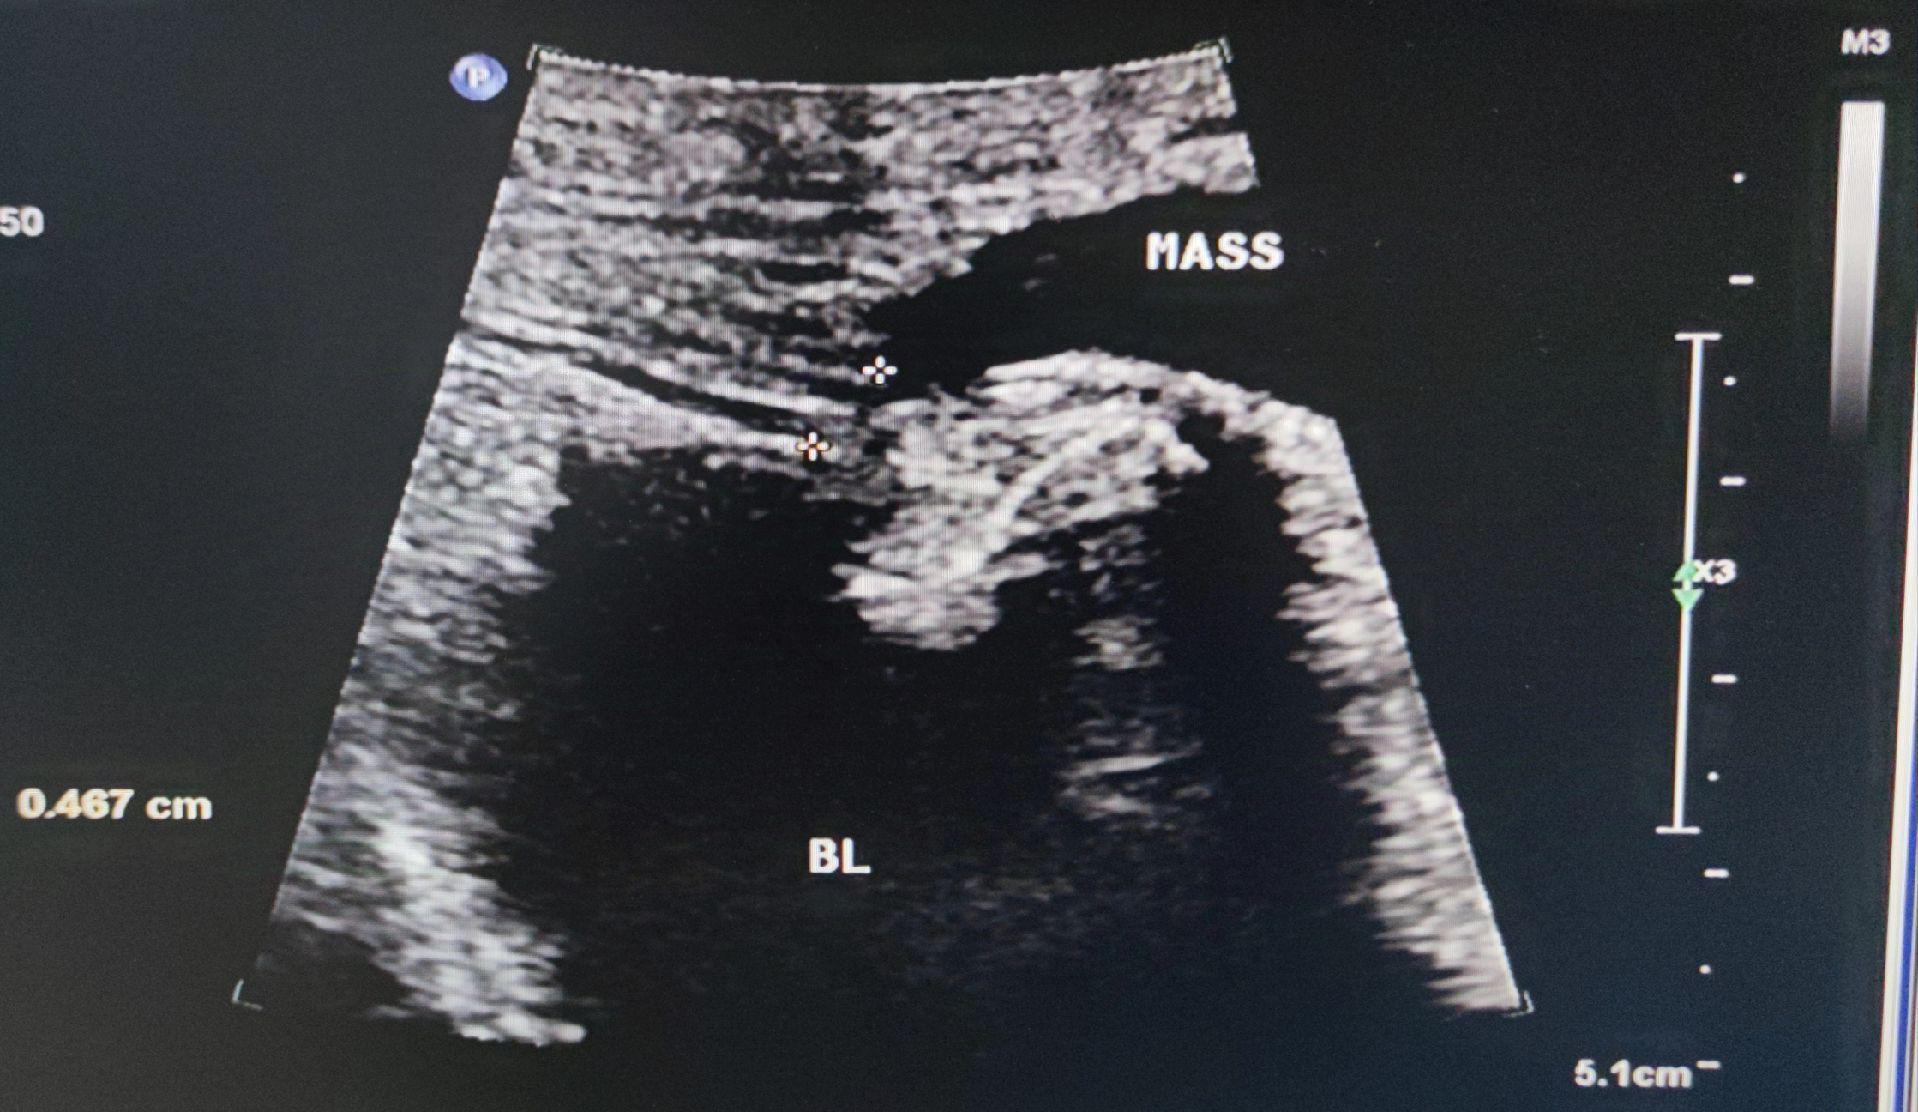

子宫圆韧带囊肿。女,41岁,腹股沟去包块来检查 子宫圆韧带囊肿又叫Nuck囊肿,少见。囊肿大小及形态不随体位改变而变化,有别于腹股沟斜疝